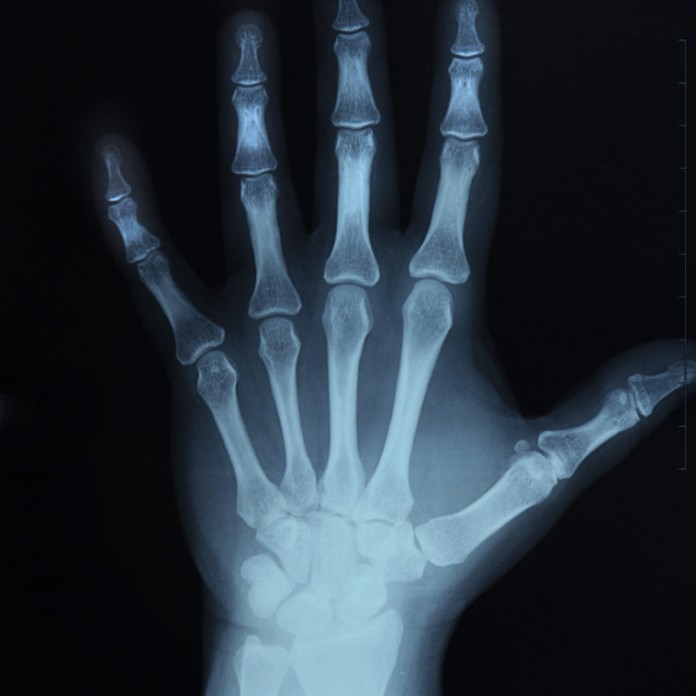

Investigadores coreanos creen que la proteina ‘DJ-1″ puede ser utilizada para promover la formación de nuevo tejido óseo en pacientes que sufren de osteoporosis mediante la mejora de la comunicación entre el hueso, las células (osteoblastos) y los vasos sanguíneos (endotelio). La investigación fue publicada en Nature Communications.

Profesor Suh Pann-Gill y el Dr. Kim Jung-Min en la Facultad de Ingeniería Nano-Bioscience and Chemical, Ulsan Instituto Nacional de Ciencia y Tecnología (UNIST) identificó DJ-1 como un mediador de la diafonía entre los osteoblastos y endoteliales células de cribado de moléculas secretadas de células no diferenciadas aún esqueléticos humanos.

Estas células esqueléticas, también conocidas como células madre mesenquimales, tienen la capacidad de convertirse en células óseas (osteoblastos de pleno derecho).

Los investigadores demostraron que DJ-1 estimula la diferenciación de las células esqueléticas aún no diferenciadas en células óseas por fibroblastos, células de activación que a su vez garantizar un crecimiento de tejido conjuntivo. Trabajar con roedores, que fueron capaces de descubrir funciones extracelulares previamente indefinidos de DJ-1, para promover la angiogénesis y la osteogénesis, lo que sugiere DJ-1 pueden tener potencial terapéutico para estimular la regeneración ósea.